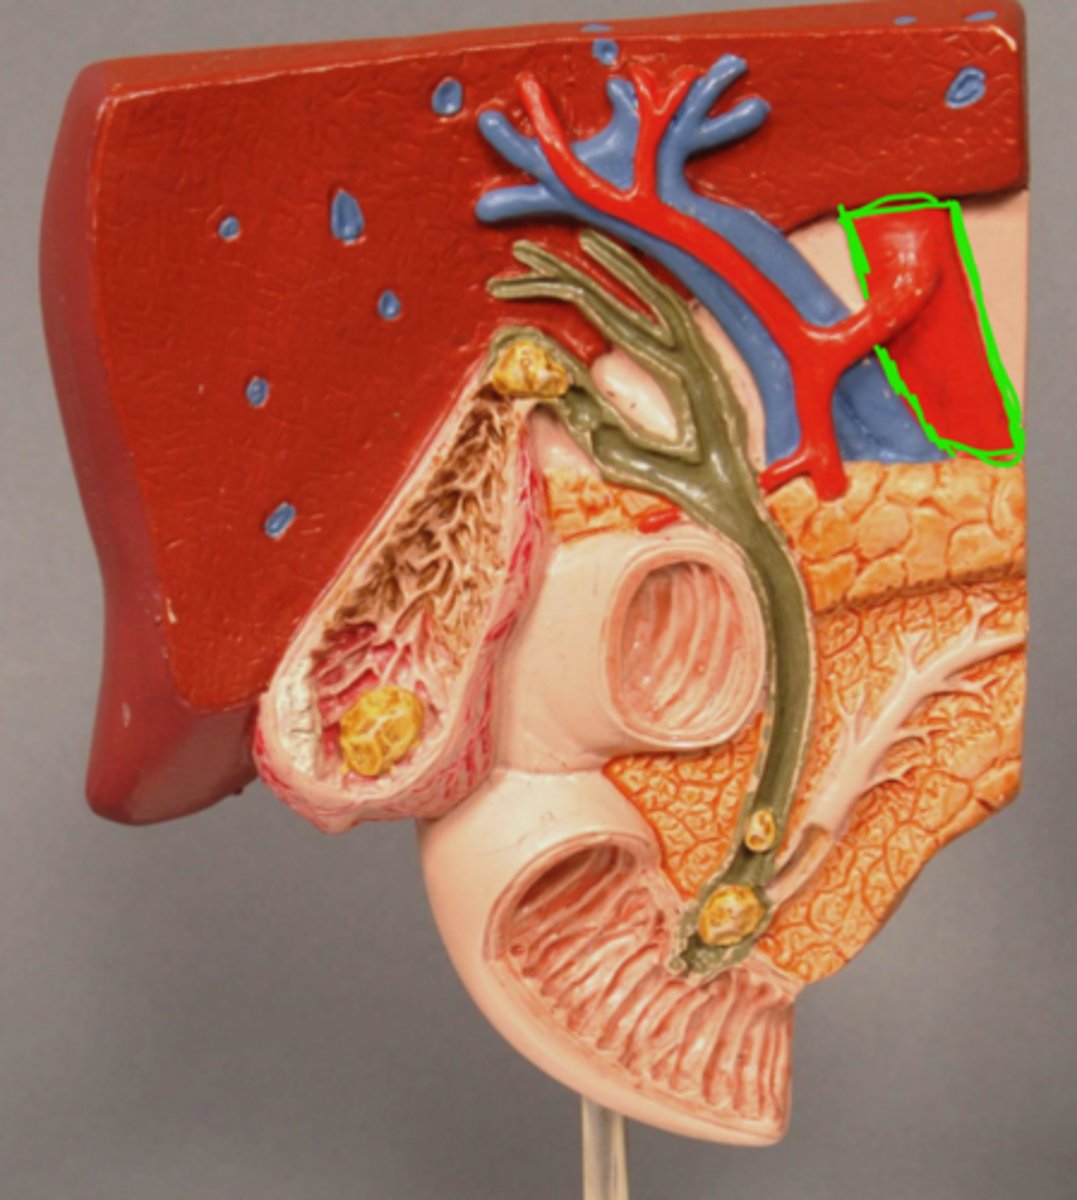

Abdominal Aorta

Hepatic Portal Vein